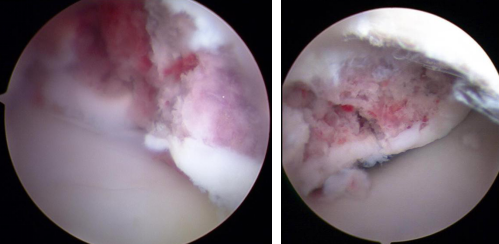

术前影像

距骨骨折进行手术治疗有一个比较棘手的并发症,就是骨折不愈合和距骨缺血性坏死,治疗中精准的复位固定和尽可能地减少对距骨血供的伤害是关键。讨论后,石荣剑副院长曹广超主任团队决定利用踝关节镜联合机器人治疗距骨骨折。术中,进行关节镜下探查清理,克氏针撬拨复位骨折端;打入克氏针固定骨折端,再在机器人的精准辅助下打入导针,拧入螺钉。手术仅数个0.5厘米切口,创口微乎其微,患者非常满意。

术前设计